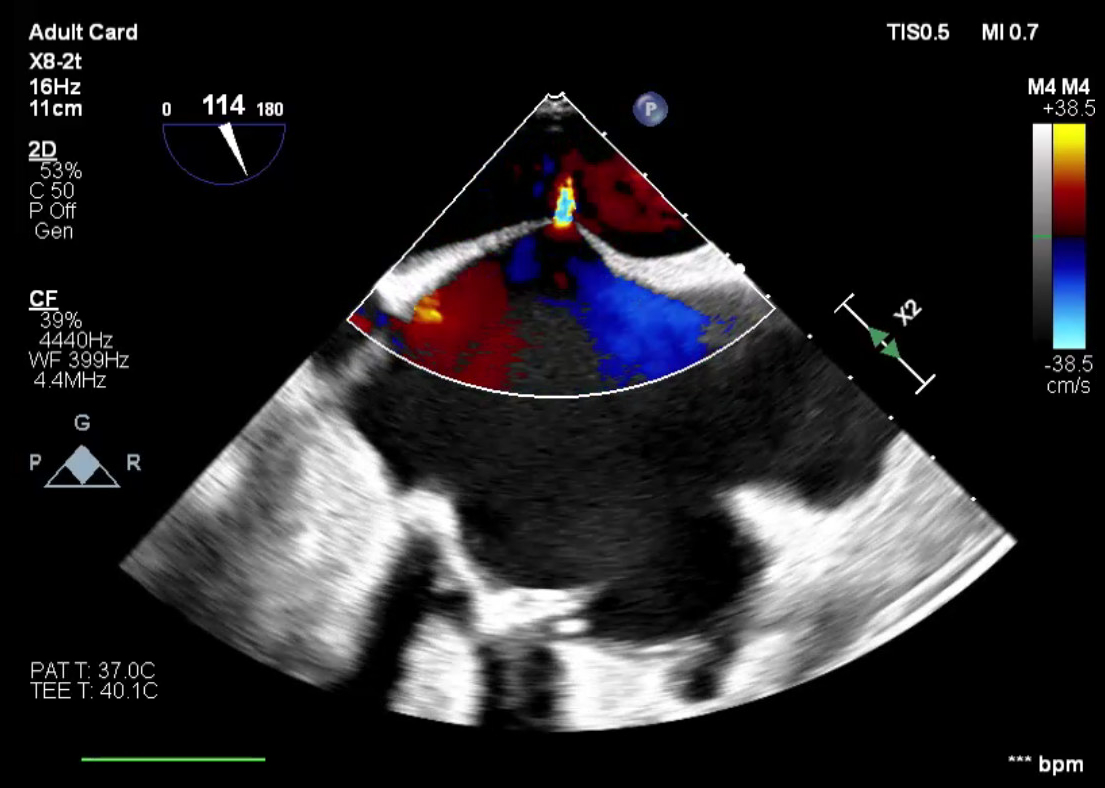

Abstract Body (Do not enter title and authors here): Case Description: A 54-year-old male with ESRD on hemodialysis, tricuspid valve endocarditis status post bioprosthetic valve replacement, and atrial fibrillation status post catheter ablation one month prior, underwent elective Watchman device implantation. Following successful device placement, the patient continued to require ventilator support. Intra-procedural TEE revealed a known iatrogenic atrial septal defect (iASD) from prior ablation with a moderate right-to-left shunt and a peak gradient of 16 mmHg. The bioprosthetic tricuspid valve demonstrated severe stenosis. Additional findings included moderate-to-severe tricuspid regurgitation, a severely dilated right atrium, and preserved left ventricular ejection fraction. The patient remained ventilator-dependent and developed septic shock within 24 hours secondary to pneumonia. Despite dialysis and antibiotic therapy, hypoxia persisted. The right-to-left shunt across the iASD, driven by elevated right atrial pressure from severe tricuspid stenosis, was identified as a major contributor. On hospital day 9, the patient underwent transcatheter tricuspid valve replacement. Following the procedure, he improved rapidly, was extubated within 48 hours, and was discharged four days later, off supplemental oxygen and ambulating with support. At 45-day follow-up, he remained asymptomatic. TEE showed a well-functioning tricuspid prosthesis, moderately dilated right atrium, and two small ASDs with predominantly left-to-right flow.